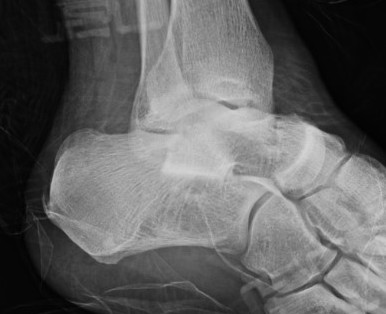

Medial subtalar dislocation

1. Medial

- calcaneum dislocated medially

- more common

- forced inversion in plantar flexed position